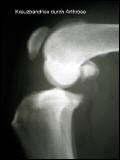

Der Kreuzbandriß beim Hund ist im Gegensatz zum Menschen in 90 % der Fälle nicht durch einen Unfall verursacht sondern eine Folge von degenerativen Prozessen im Gelenk wie z. B. einer Gelenksarthrose. Begünstigt wird diese Erkrankung z. B. durch Übergewicht. Deshalb geht der betroffene Hund meistens ohne deutlich erkennbare Ursache plötzlich lahm. Beim Neufundländer und Boxer ist eine genetische Anlage bewiesen. Generell gilt aber, dass vor allem ältere kastrierte Hündinnen (> 6-7 J) mit Übergewicht betroffen sind. Die betroffenen Tiere zeigen eine zumeist deutliche Lahmheit am betroffenen Hinterbein. Die Diagnose wird beim Tierarzt durch eine Ganganalyse, den Sitztest, eine umfassende klinische Untersuchung (z. B. Schubladenphänomen, Tibiakompressionstest) und Röntgendiagnostik gestellt. Eine Röntgenuntersuchung in mind. 2 Ebenen ist zwingend erforderlich um weitere Erkrankungen (z.B. eine Arthrose oder eine OCD) festzustellen.